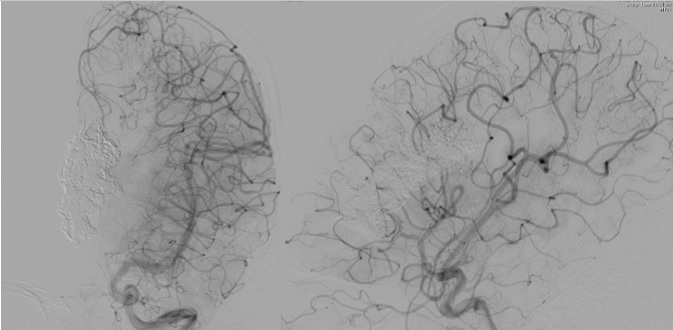

第一子出産から1ヶ月後に小脳のAVMの破裂により突然の激しい頭痛とめまいが起こり受診しました。マイクロカテーテルを流入動脈(ナイダスへ入る動脈)の末梢まで挿入し、NBCAとオイドラギット(Onyx類似の薬剤)を注入しAVMを完全に閉塞しました。その後再発なく7年が経過しています。

脳梁の大きなAVMが破裂し紹介入院となりました。3~4ヶ月ごとに3回に分けてOnyxを注入しAVMが小さくなった時点でガンマナイフの照射を行い、AVMはほぼ消失しました。現在、後遺症は全くありません。